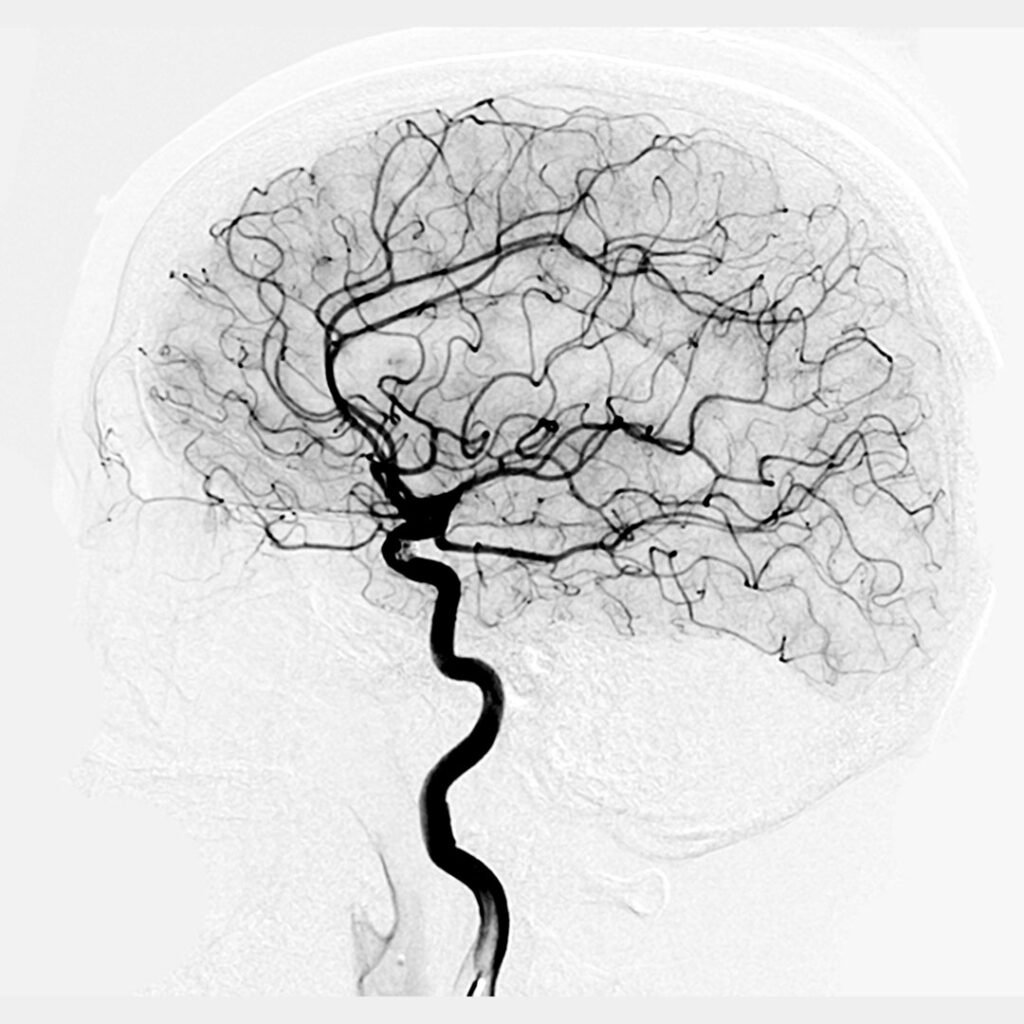

Medical angiography scan showing intricate blood vessels in the human brain, representing expert Angiography in Indore by Dr. Akhilesh Jain.

3. Cerebral Angiography – Evaluates the blood supply to the brain and identifies stroke risk.